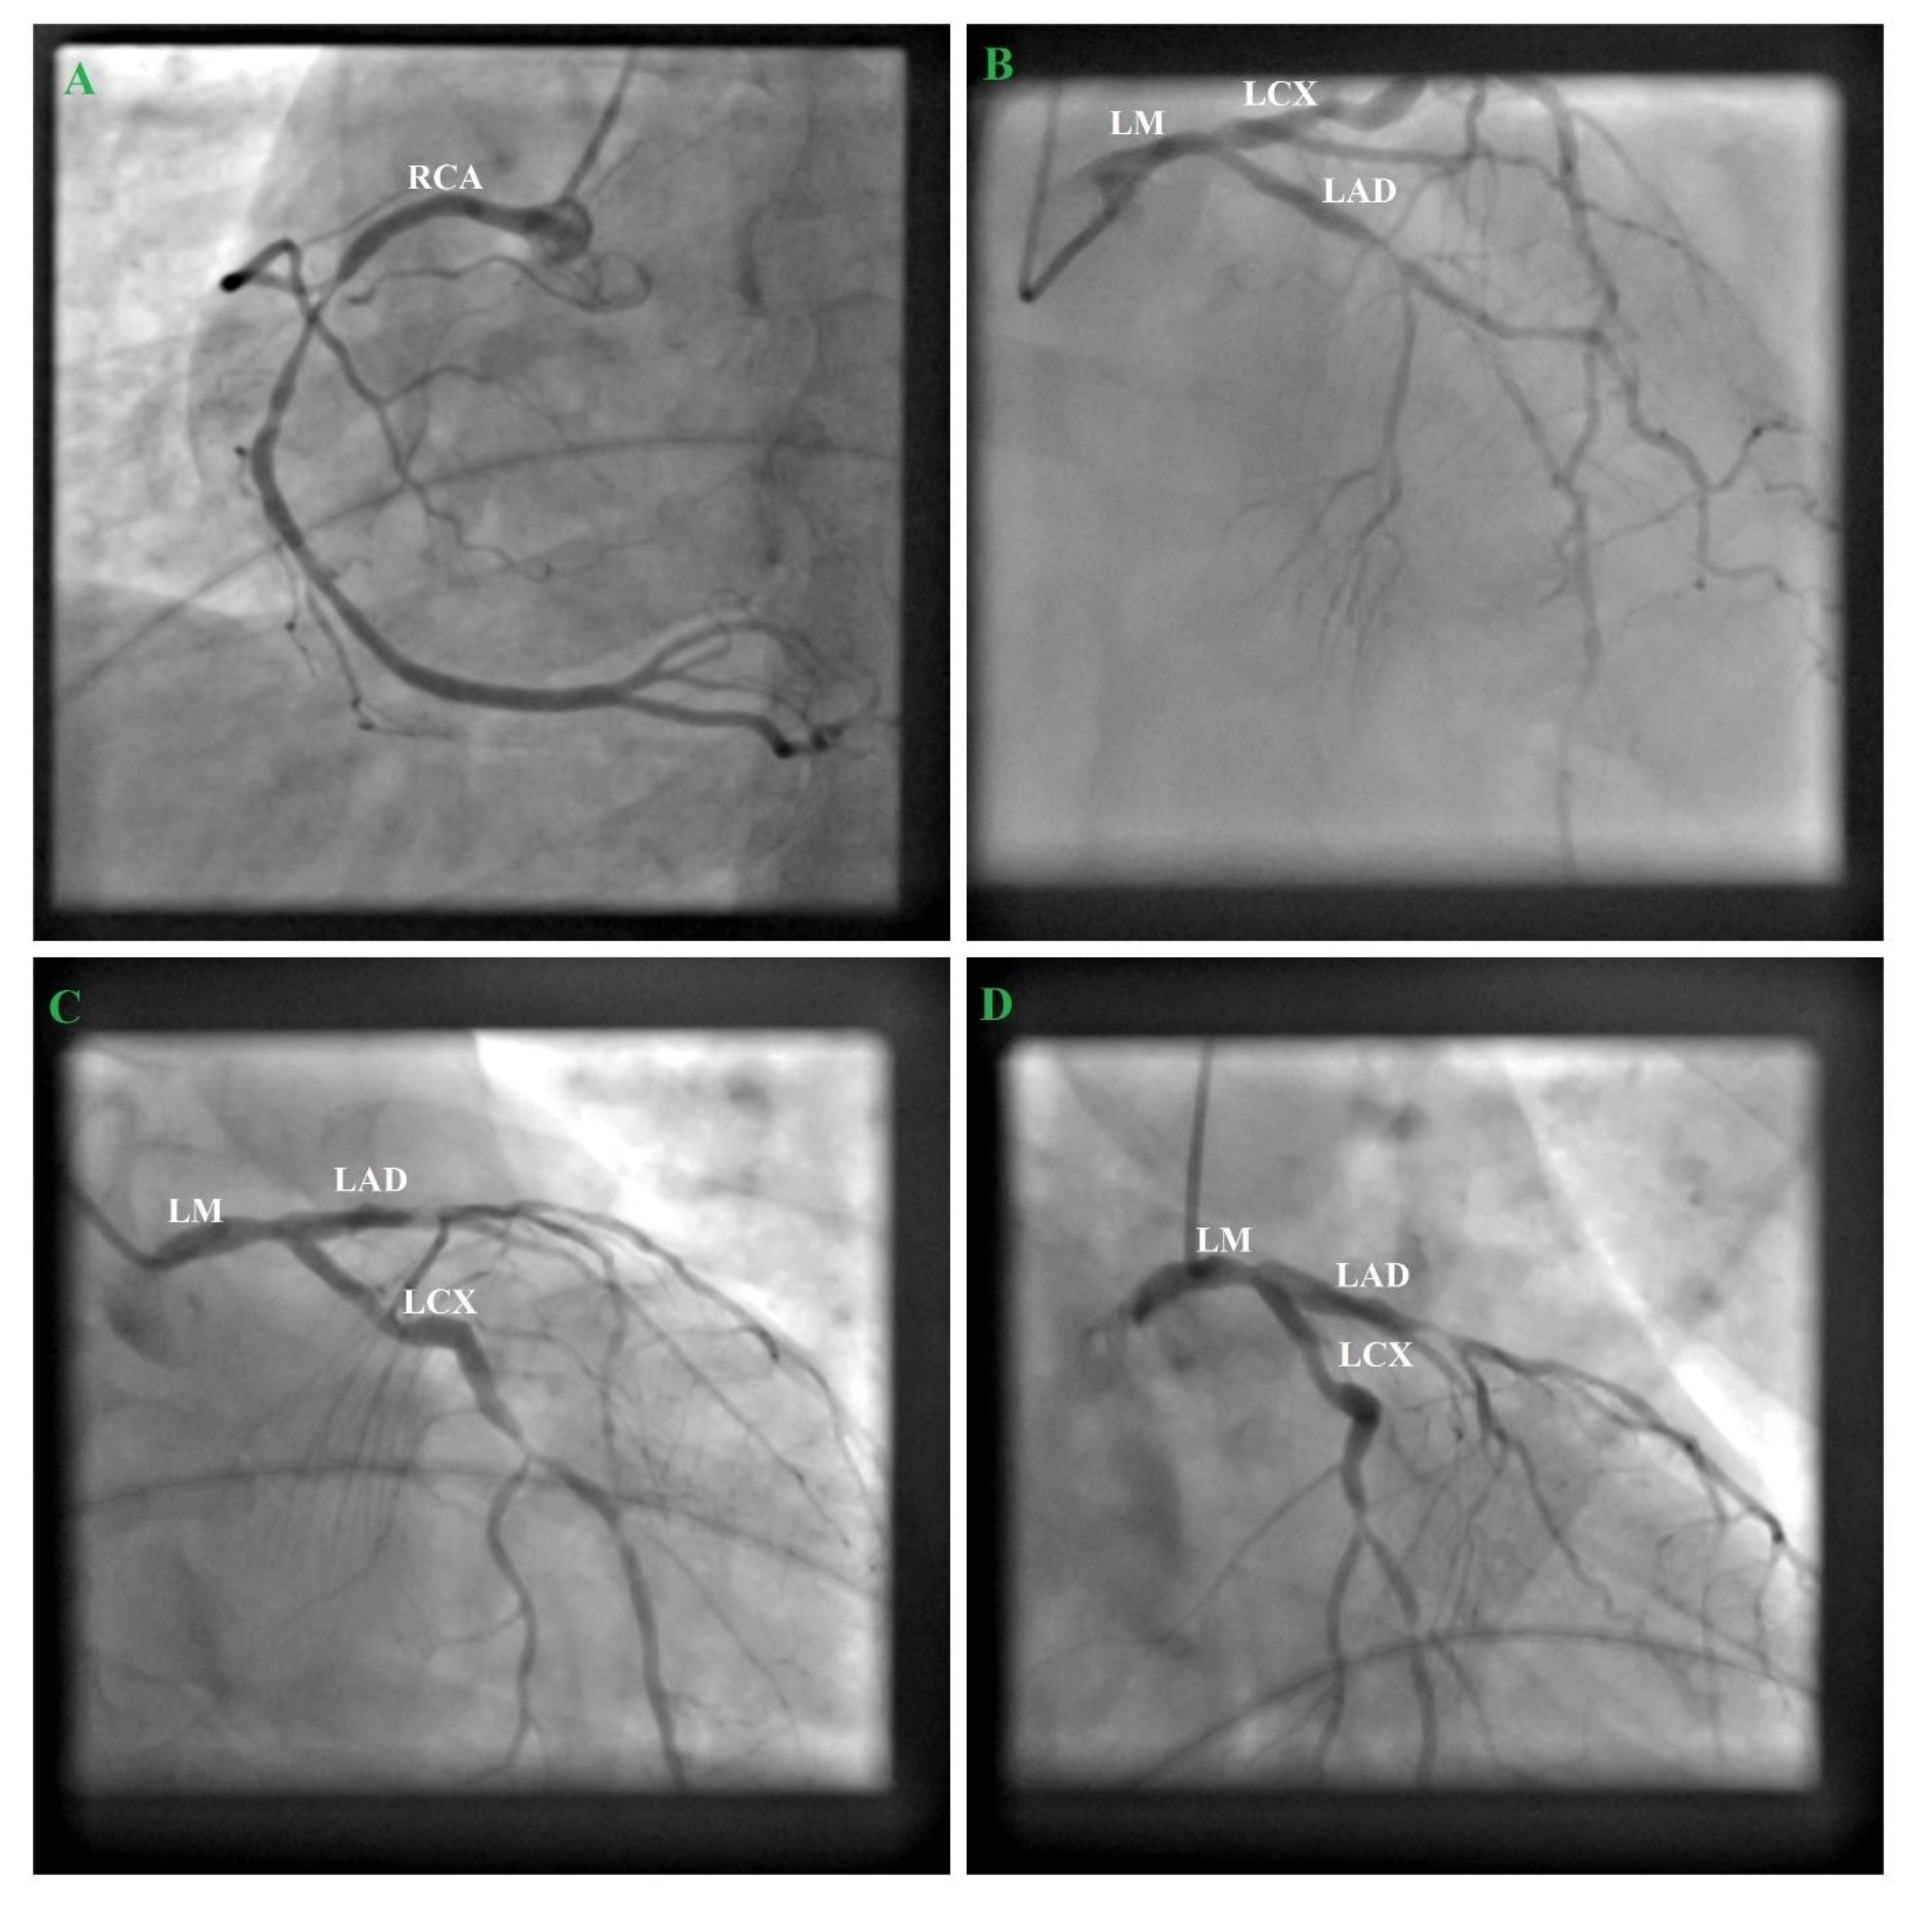

Frontiers Hemodynamic Relevance Of Anomalous Coronary Arteries Originating From The Opposite Sinus Of Valsalva In Search Of The Evidence Cardiovascular Medicine